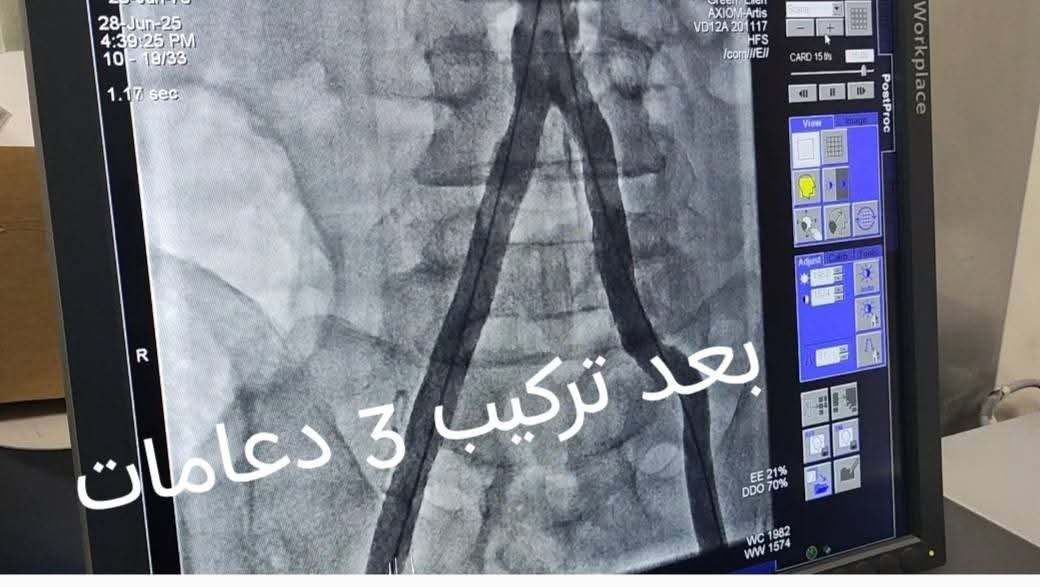

Challenging Cases Azil Hospital

Endovascular Team